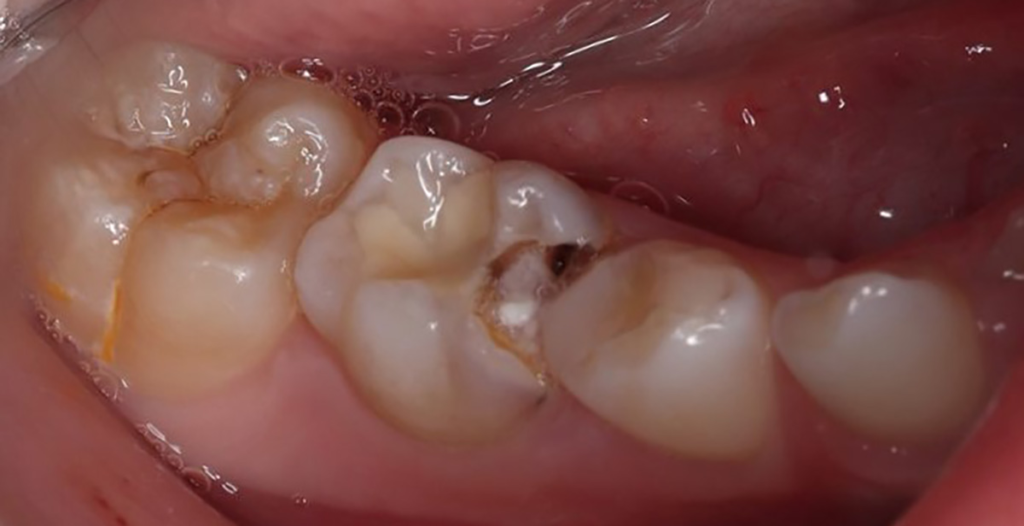

Als Ersatz für die inzwischen insuffiziente Kompositfüllung (Abb. 7) wurde mit dem Patienten und seinen Eltern eine definitive Versorgung mit einer konfektionierten Kinderzirkonkrone (NuSmile ZR Zirconia Posterior, USA) diskutiert und diese nach ihrer Einwilligung mit Fuji I (GC, Tokyo, Japan) eingesetzt (Abb. 8). Nach weiteren 3 und 6 Jahren wurden erneut Kontrollröntgenaufnahmen und klinische Bilder angefertigt (Abb. 9 bis 17). Dabei war auch die symmetrische Nichtanlage des unteren rechten 2. Prämolars zu beobachten (Abb. 11, 13 und 14).

Bislang konnte keine weitere Progression der Wurzelresorption während des Beobachtungszeitraumes festgestellt werden. Der linke 2. Milchmolar zeigt eine geringgradige Infraokklusion (Abb. 12 und 15). Da der entsprechende Oberkieferprämolar adäquat durch die Randleiste des Nachbarzahnes abgestützt ist, ergibt sich zum jetzigen Zeitpunkt noch keine Gefahr einer ungewollten Elongation (Abb. 15 und 16).